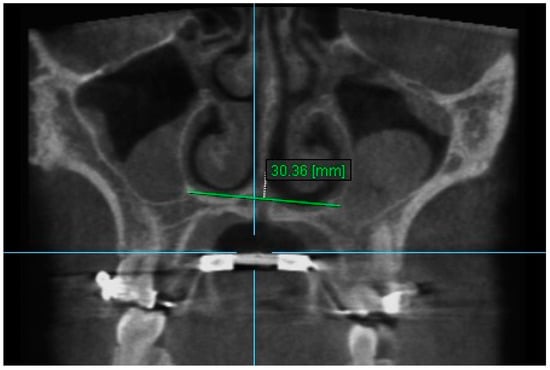

1. Nasal Width 1: The maximum lateral interior width of nasal cavity on coronal slice through the center of the mesial buccal root of the first permanent molar (Figure 3).

Figure 3.

Nasal Width 1.

2. Nasal Width 2: The maximum lateral interior width of nasal cavity on coronal slice through the center of the root of the second premolar (Figure 4).

Figure 4.

Nasal Width 2.